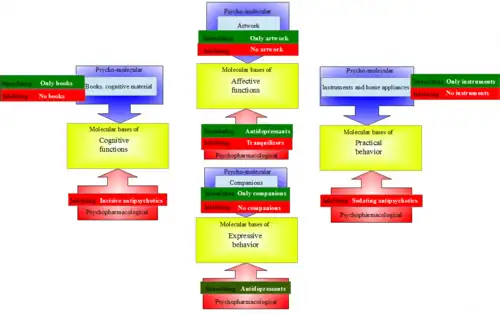

- psychopharmacological techniques, using drugs that act specifically on different constitutive axes of personality (cognitive, practical, affective, expressive);[90]

- psycho-molecular method, influencing the activity of specific neurotransmitter systems through specific psychological tasks;[84][91] the method is part of psycho-molecular medicine, which integrates details of molecular structure into upper, psychosocial levels of the human organism.[92]

Psycho-molecular therapy

The psycho-molecular method uses specific tasks in order to influence specific neurotransmitter systems.[84] Through the control of the environment which is selectively enriched or deprived, some of the subject's brain areas can be stimulated or inhibited systematically, leading to changes in the seric levels of the metabolites of certain neurotransmitters, associated with clinical improvement in burnout individuals.[84] Behavioral approaches have a critical impact on molecular patterns of autoregulation, leading to the assumption of a bio-psycho-socio-molecular model of autoregulation, including stress and pain. Thus, molecules and behavior may be seen as two sides of the same problem in pain and stress relief.[91]

Psycho-molecular techniques can be stimulating or inhibiting. Stimulating techniques involve the presence of environmental materials that allow a single type of activity (cognitive, practical, affective, or expressive). For example, the subject sits in a room where he has nothing else to do except read. Inhibiting techniques selectively exclude from the subject's environment materials that allow one specific type of activity, leaving all the other types available (for example, the subject can look at paintings, watch sports on TV, prepare his food, but has no books or other learning material in his room).[84]

Stimulating techniques are:[84]

- Practical technique, that involves living at a farm where the sole activity is food foraging and preparation;

- Expressive technique, that involves relational experiences in a room where the subject lives together with another person;

- Cognitive technique, that puts the subject in a room where books and other learning material are the only object of activity;

- Affective technique, that involves placing the subject in a room where there are only art works and audio and video hardware for listening music and watching movies.

Inhibiting techniques are:[84]

- Cognitive technique, that excludes from the environment textbooks and other objects of cognitive behavior;

- Affective technique, that excludes sources of affective and aesthetic evaluation;

- Practical technique, that excludes home appliances, cleaning activities, preparing food, and setting the table;

- Expressive technique, that places the subject in a room with all facilities, but where interactions with other persons are reduced at a minimum.

The control of the effects of these techniques is made through clinical scales and biochemical tests monitoring serum levels of metabolites of several stimulating and inhibiting neurotransmitters: dopamine (homovanillic acid), norepinephrine (3-methoxy-4-hydroxyphenylglycol), and serotonin (5-hydroxyindoleacetic acid).[84] Although less spectacular than with psychopharmacological methods, the effect of psycho-molecular therapy is more complex and natural, and needs to be associated with psychopharmacological and psychotherapeutic treatments.[84]